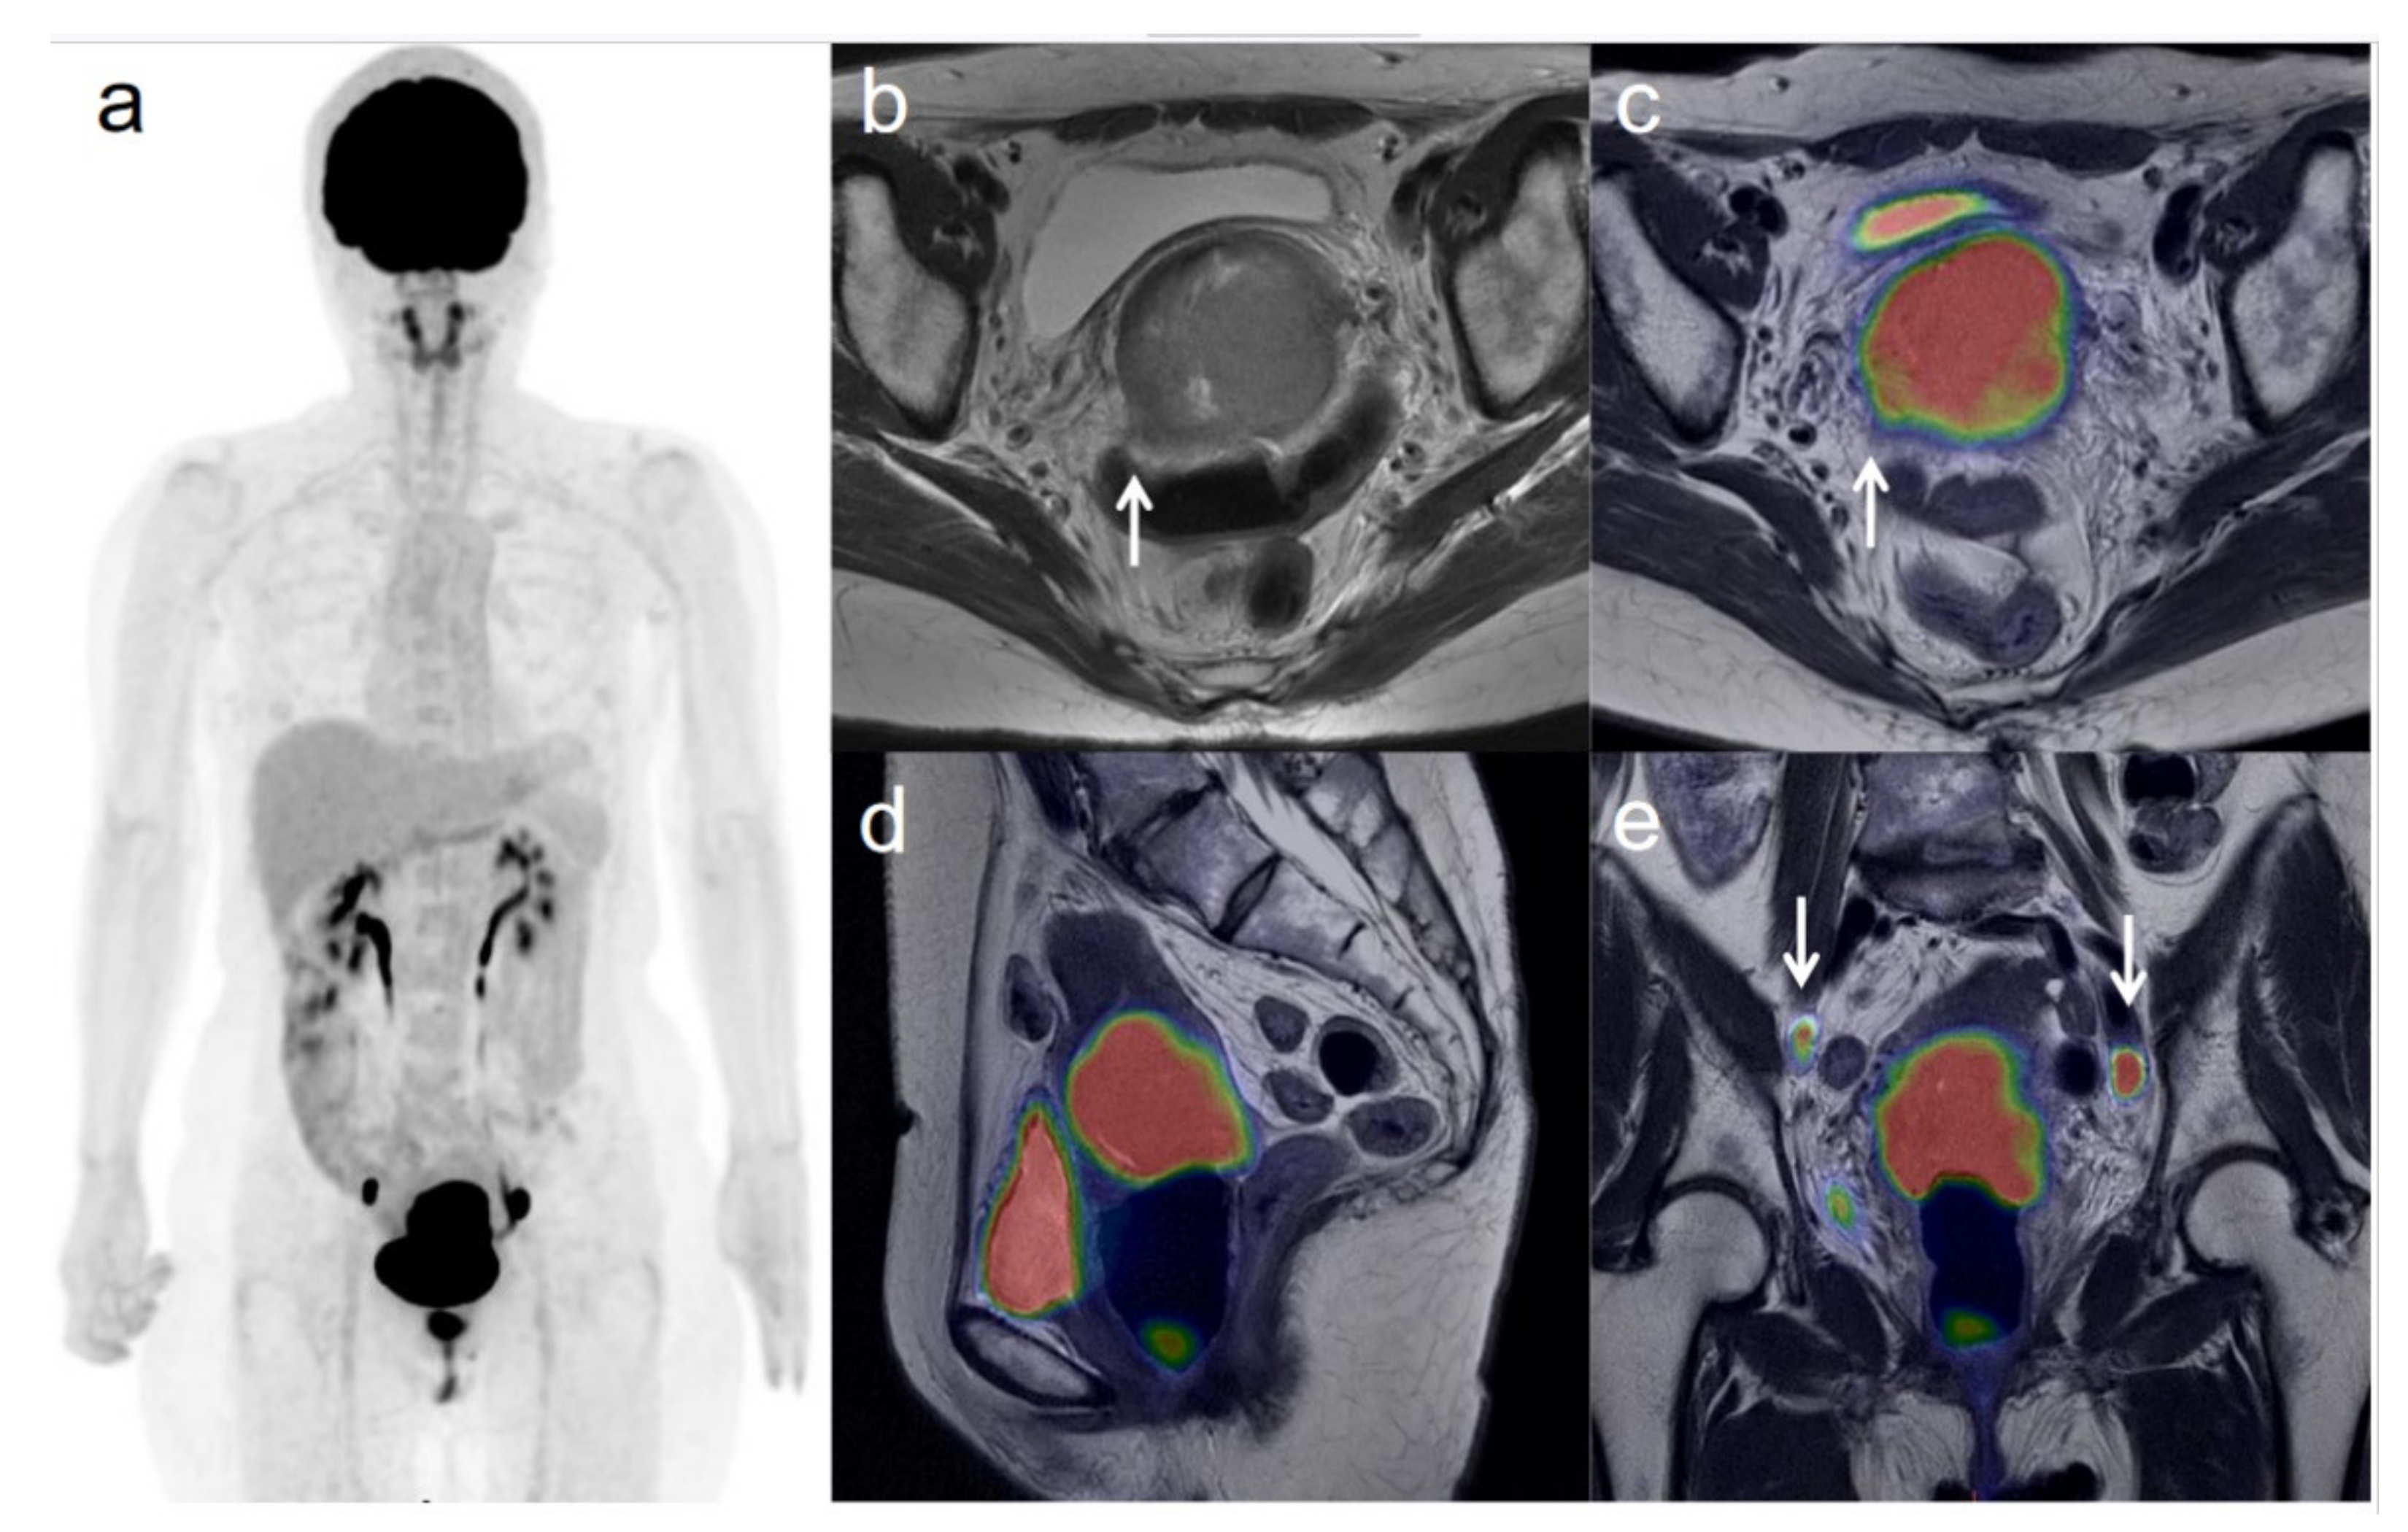

3.3. Revised FIGO Staging

Figure 2. A 62-year-old woman with stage IVB cervical cancer with invasion into the pelvic side wall. (a) 18F-FDG PET image shows FDG uptake by tumor in the cervical cervix (arrow) and a right inguinal lymph node. (b) Axial T2-weighted pelvic MR image shows disruption of the right cervical stroma by the tumor and extension into the pelvic side wall (arrow). (c) Axial T2-weighted PET/MR image shows FDG uptake by the tumor, which invades the right cervical stroma and extends into the pelvic side wall (arrow). These appearances are consistent with the clinical findings. (d) Sagittal T2-weighted PET/MR image shows FDG uptake by the cervical tumor and invasion into the bladder (arrow). (e) Coronal T2-weighted PET/MR image shows invasion of the bladder by the cervical tumor and FDG uptake by a right inguinal lymph node (arrow).